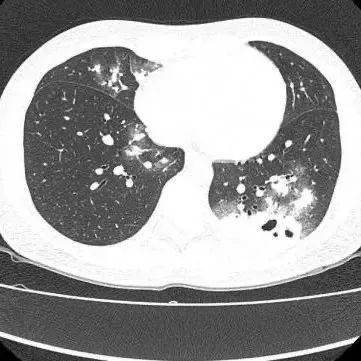

胸部CT显示其双肺多发感染

伴多发空洞形成

医生查房时,捕捉到CT上形似“鬼脸”的特殊影像(即“鬼脸征”),并伴有“晕伦征”,高度怀疑隐球菌肺炎。医生追问夏女士近期是否曾接触鸟类、禽类及饲养宠物,夏女士否认。

在免疫功能正常的患者中,肺部常见的表现为单发或多发的结节,有时伴有晕征(指结节周围的低密度环),结节内可能见到空洞,胸膜下多见。在免疫功能缺陷(如恶性肿瘤、白血病等)的患者中,可能表现为弥漫的、大片的肺炎样改变。